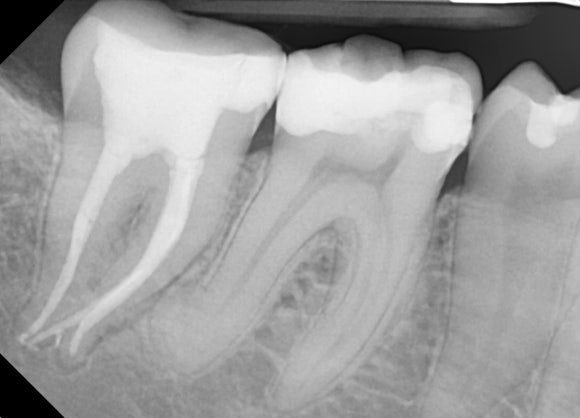

영국에서 거주중이신 이 환자분은,

오른쪽 아래 어금니를 치료 받으신 후

통증이 재발하셨다고 합니다.

주치의 선생님이

내부를 보시고

기존에 치료했던 것을 모두 제거해주셨다고 합니다.

이제 다시금

재신경치료를 받으실 때가 되셨는데요,